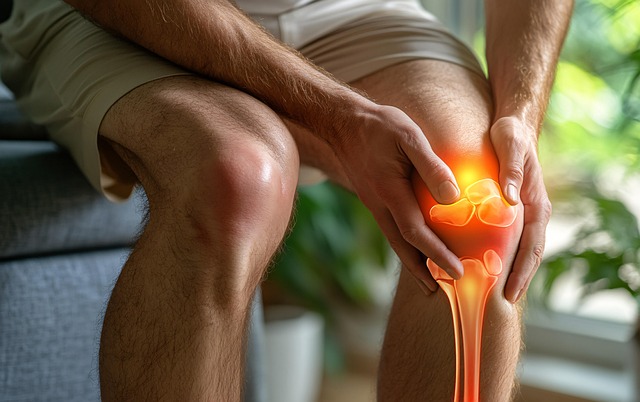

무릎통증 치료방법, 단계별 접근이 필요

통증의 원인과 정도에 따라 치료는 다양하게 구성된다.

- 약물치료: 비스테로이드성 소염제(NSAIDs), 근육 이완제, 국소 진통 패치 등을 사용

- 물리치료: 냉온 찜질, 전기자극, 레이저 치료 등으로 통증 완화 및 회복 도모

- 운동요법: 대퇴사두근 강화운동, 수영, 실내 자전거 등의 무릎부하 감소 운동 병행

- 주사치료: 스테로이드, 히알루론산, PRP 등 관절내 주사 치료 가능

- 수술치료: 연골 손상이 심각하거나 보존 치료 효과가 없을 경우 관절경 수술 또는 인공관절 수술 시행